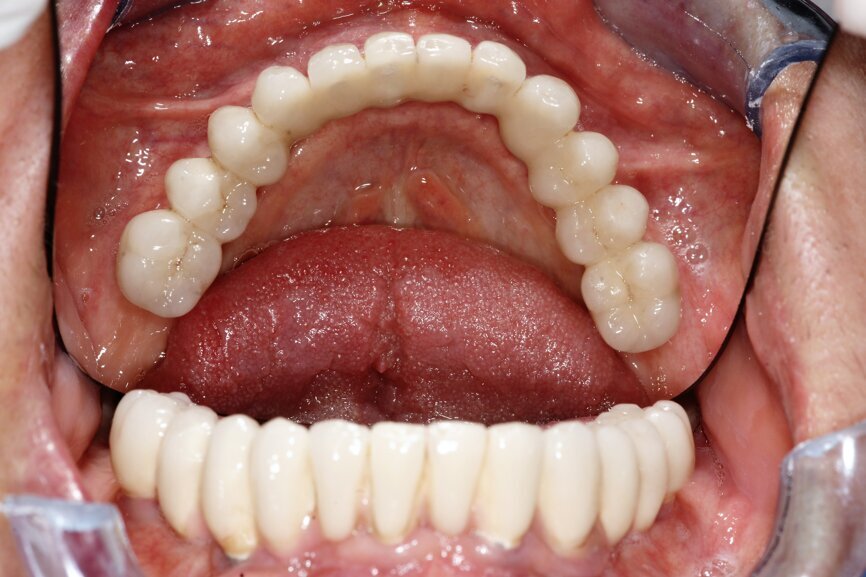

przygotowanej wcześniej protezie czasowej metodą bezpośrednią. Czasowe uzupełnienie protetyczne osadzono, używając cementu tymczasowego (Ryc. 5 i 6). Zlecono wykonanie zdjęcia techniką CBCT (Ryc. 7). Wizytę kontrolną wyznaczono następnego dnia, a szwy zostały usunięte po 10 dniach.

Po upływie 3 miesięcy czasowe uzupełnienie protetyczne (Ryc. 8) zostało wymienione na cementowaną pracę ostateczną (Ryc. 9),

W kwietniu 2017 r. został wykonany status periodontologiczny pozostałego uzębienia i wszczepionych implantów (Ryc. 12) i ponowne badanie CBCT (Ryc. 13- 15). Stan 3 lata po zabiegu przedstawiono na rycinach 16-18. Pacjentka jest ujęta w programie Recall w cyklu 6-miesięcznym od dnia wykonania zabiegu.